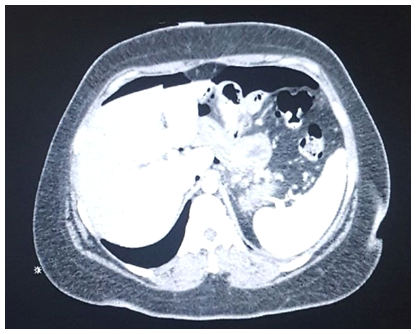

J.N.M.P., 33 years old, female, was submitted to a laparoscopic Roux-in-Y Gastric Bypass due to severe obesity (BMI 41 kg/m2) and hepatic steatosis. On the seventh postoperative day (PO), she complained of bilateral shoulder pain. There were no significant alterations on the physical examination, no fever and normal pulse. The secretion present in the drain was serous and methylene blue oral intake test was negative. Laboratory tests revealed leukocytosis of 13,000 without other changes. Abdominal CT scan with oral and intravenous contrast showed no signs of leakage, free intracavitary fluids or collections but the presence of a large volume pneumoperitoneum, not expected for a seventh postoperative day. Leading with a hypothetical fistula, consistent with the indirect CT findings, and in the absence of sepsis signs, we started a treatment with fasting, antibiotic therapy and parenteral nutrition. Three days later, there was 80 to 90% improvement of the clinical onset of shoulder pain, and reduction of leukocytosis. Eight days later, another CT showed an important reduction in the pneumoperitoneum volume, which allowed to reestablish oral intake. The patient had a good evolution. Another Tomography, fifteen days after hospital discharge, showed no pneumoperitoneum (Figures 1-4).1–3

Figure 3 TC ABDOME.

The pneumoperitoneum, disproportional to the postoperative time, is an indirect imaging criteria of digestive fistula, in the gastric bypass it is not different. In this case, non-surgical treatment has been considered one of the options, avoiding the morbimortality of reoperations and offering a safe treatment for the patient.